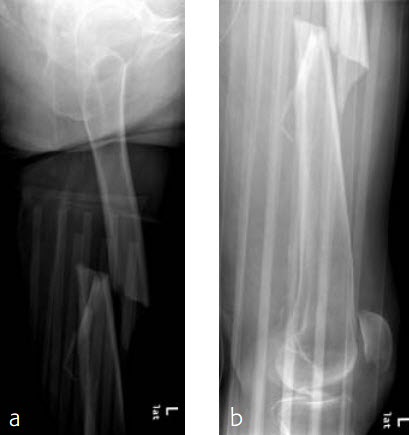

Case 2: Left femur fracture

A 70-year-old female patient suffered an AO 32-B3 fracture of the left femur (Figs 3 and 4). Fixation with the FRN for a tip of the trochanter entry point (nail diameter 10 mm; nail length 400 mm; reaming to 12 mm) in standard interlocking mode (Figs 5 and 6). Proximal locking with antegrade and transverse dynamic locking positions. Distal locking with two lateral to medial locking screws in static locking position.